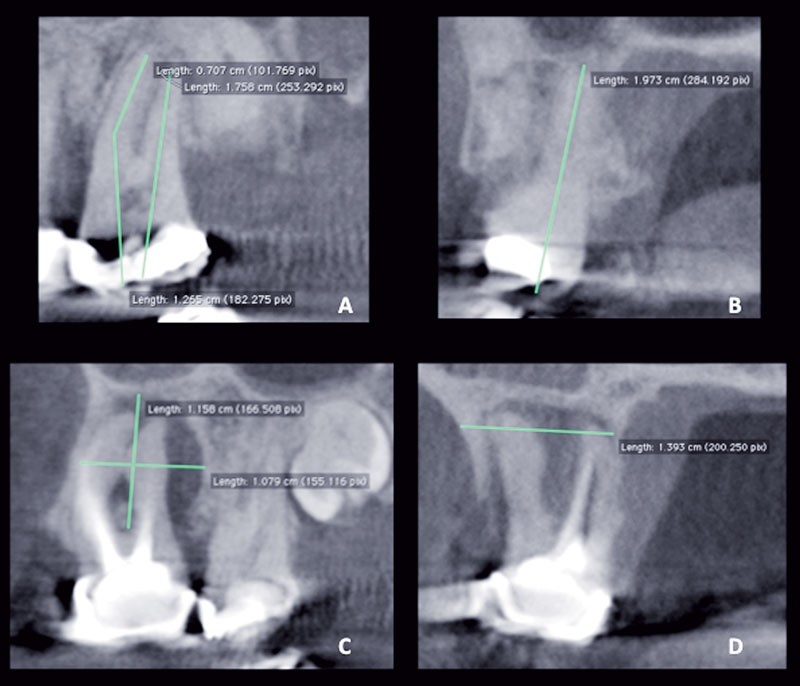

La tomographie volumique à faisceau conique est l’examen complémentaire à privilégier dans de nombreuses situations endodontiques : aide au diagnostic, bilan préchirurgical, visualisation de l’anatomie, suivi de traitement…